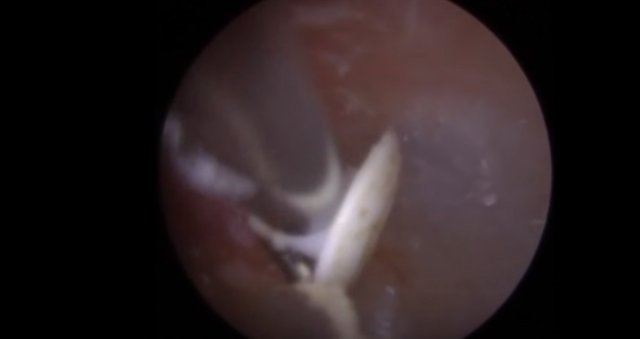

30 yıl boyunca geçmeyen bir baş ağrısı ile yaşayan bir kişi gittiği doktoru şoke etti. Yıllarca baş ağrısı çeken 59 yaşındaki adamın yaşadıkları kan dondurdu. Adamın kafasından öyle bir şey çıktı ki, doktorlar bile şaştı kaldı. İşte şoke eden olayın detayları...